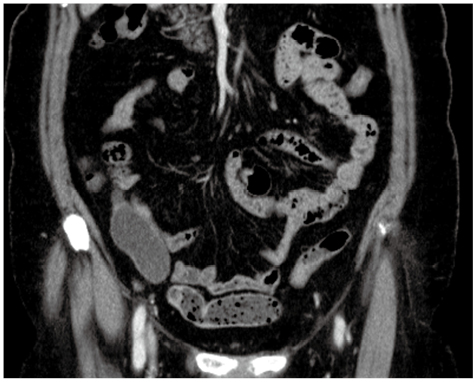

症例1

症例1の患者情報

70歳代,女性。

前医にて右乳癌精査中に偶発的にS状結腸癌を指摘され,CTCを施行。

既往歴:右乳癌。

身体所見:特記所見なし。